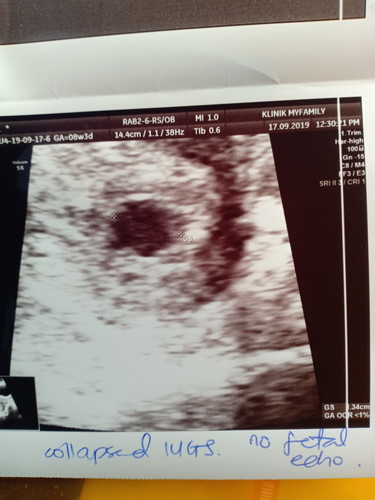

Salam semua, siapa pernah kena macam saya, hamil 8 minggu 3 hari mula ada spotting coklat dan malam tadi keluar darah macam period jeli panjang2, then terus pergi emergency hospital scan nampak kantung kosong je, dr bagi ubat duphaston, yg saya risau masih ada harapan ke baby dlm tu?

ada sis..percaya m doa je..positif mindset..kita bole jd ibu..insyaAllah sama2 ada rezeki..slagi rumahnya ada kt dlm tu insyaAllah suma selamat..percaya akn kuasa Allah..smpai harini pn sy masih percaya ank sy ada n selamat..sy 11w tp masih kantung kosong..sy yakin sgt baby ada..